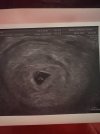

CudnieJa miałam dziś pierwszą wizytę, mamy zarodek z baaaardzo wczesnym serduszkiemz om powinno być 6+3 ale z usg wychodzi 5+5. Czuje się trochę spokojniejsza, chociaż teraz czekam czy serduszko się rozkręci

Cudne nowinyJa miałam dziś pierwszą wizytę, mamy zarodek z baaaardzo wczesnym serduszkiemz om powinno być 6+3 ale z usg wychodzi 5+5. Czuje się trochę spokojniejsza, chociaż teraz czekam czy serduszko się rozkręci

Ja byłam na wizycie w poniedziałek i to było dokładnie 5+4 i tak to wyglądałoWłaśnie odebrałam kolejny wynik progesteronu 60,bety 1599, to 161%przyrostu po 72 godz. Termin z OM wypada 8.09 5+4,14.01 mam pierwszą wizytę to ciąża z ivf trochę się stresuje mam nadzieję że na wizycie coś już będzie widać![]()

Super gratuluję ja jak będę miała wizytę to będzie to 6+1Ja byłam na wizycie w poniedziałek i to było dokładnie 5+4 i tak to wyglądało